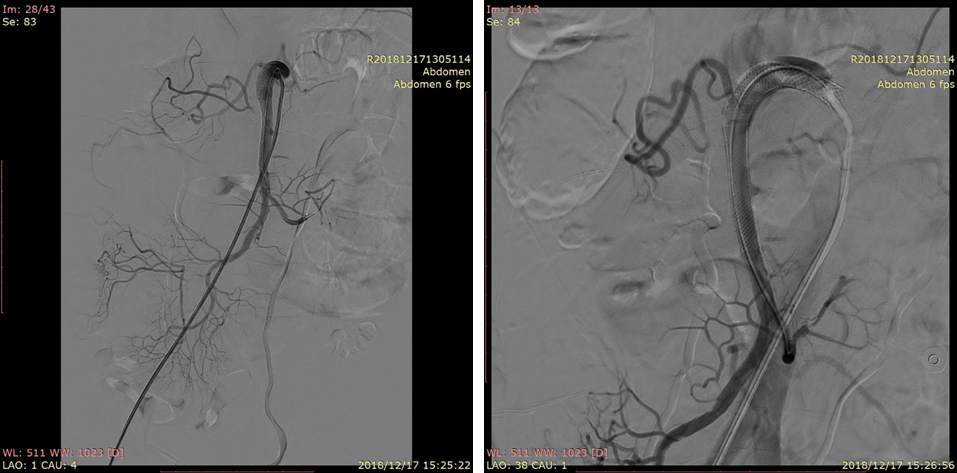

20230524DSA夹层动脉瘤

20230524DSA:VB支架植入

20230524DSA:仍有造影剂进入假腔

20230524DSA:再次送入VB